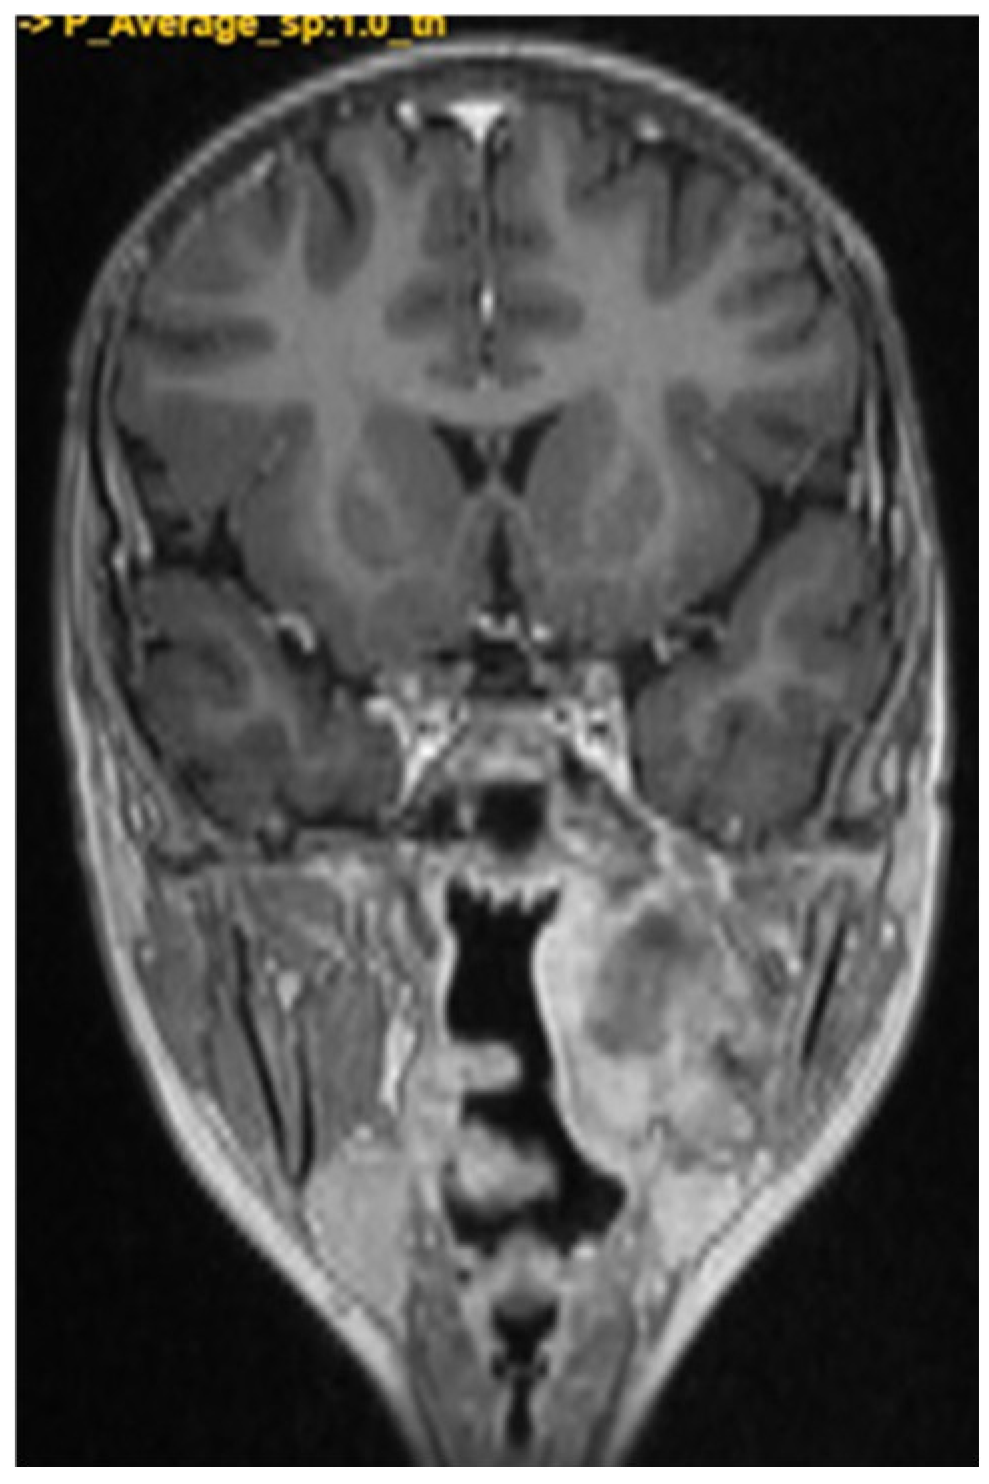

A CNS MRI was performed, which reveal a large lobulated formation in the oropharynx and nasopharynx with left tonsil involvement, spreading to the retropharyngeal space and propagating through the left Eustachian tube into the middle ear. The previously formed surgical cavity was completely infiltrated from the soft tissue tumour mass. Approximate dimensions of the lesion in the mastoid—25/45 mm. axial, 38/39 mm. coronal (Figure 6, Figure 7 and Figure 8).

Figure 6. MRI of the patient on postoperative day 17.

Figure 7. MRI of the patient on postoperative day 17.

Figure 8. MRI of the patient on postoperative day 17.